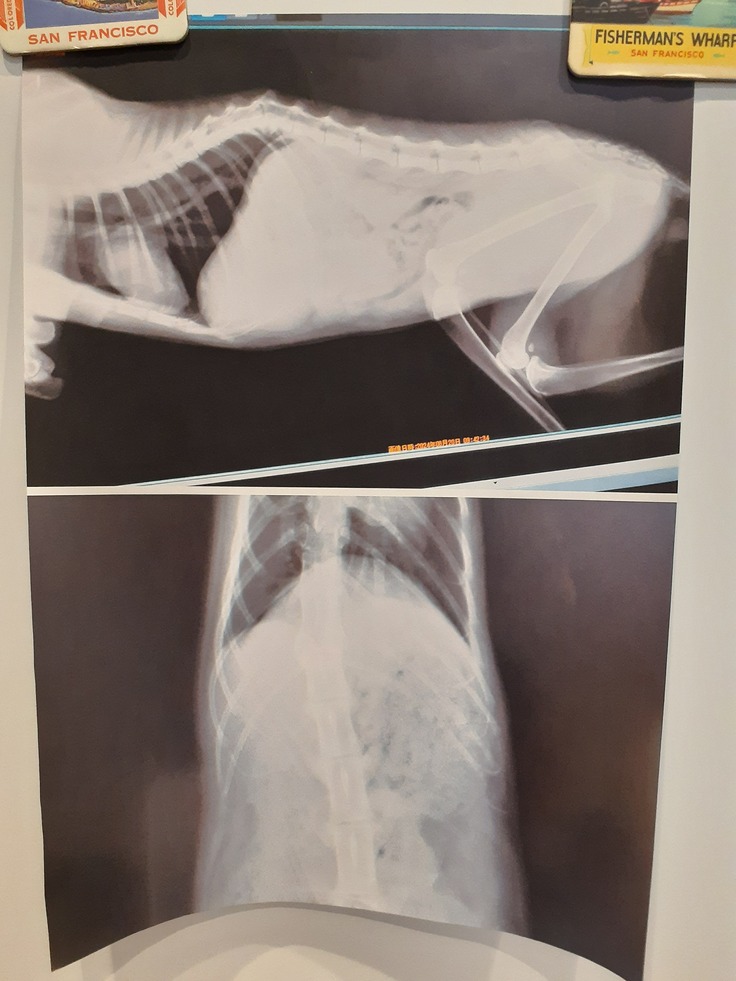

そして【そあら君】

22日夜遅くに驚くほどの血尿がありました。

エコー、尿検査をして、膀胱が汚れていること、ちょっと詰まってしまったこと、雑菌が繁殖していることが分かりました。

抗生剤等を混ぜ込んだ液体の投薬をいただいてきました。

1週間後に尿検査を予定しています。

以下【そあら君】のファイルです。